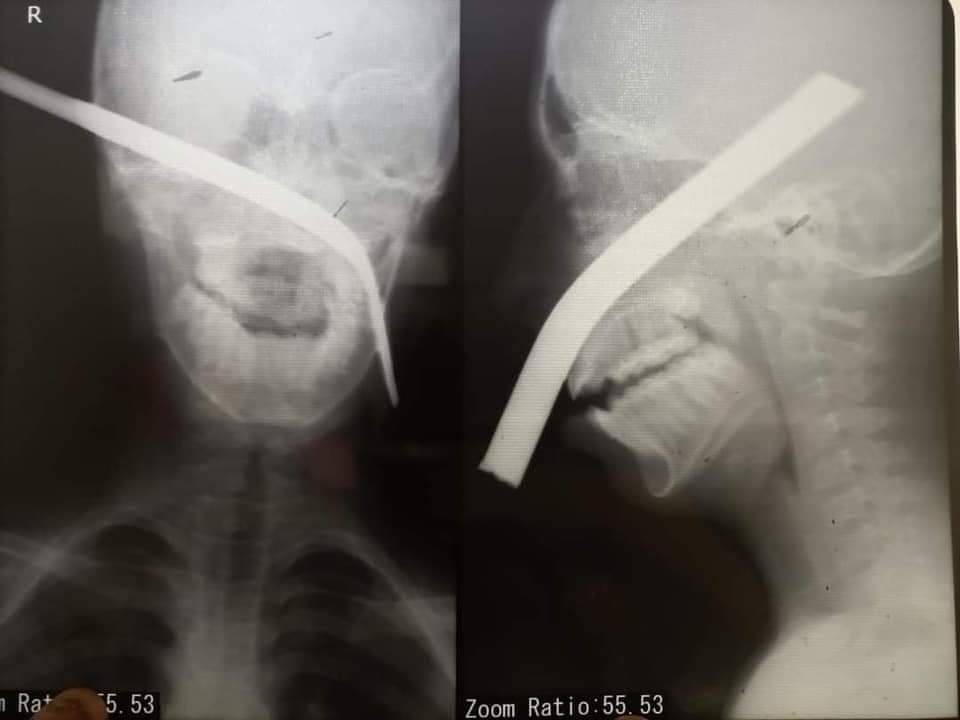

حادثة دراجة بخارية تسببت في دخول سيخ الحديد بالوجة بعظام الفك من جهة وخروجة من الجهة الاخري بجانب العين دون أي ضرر في المخ او العين

تم الاول قطع السيخ وتقصيره قبل اي شئ علشان يقدر يعمل اي اشعة وسحب كل التحاليل وعمل كل الاشعة وعرضه علي كل الاقسام المشاركة في الحالة

حالة صعب جدا تشوفها كتير في حياتك معجزة دخول سيخ بالطريقة دي وبالشكل دا والطفل conscious وبيتكلم وبيرد علينا

بعد المجهود والتحضير الجبار خرج الولد من العمليات فايق وكويس بيتكلم وشايف بوضوح